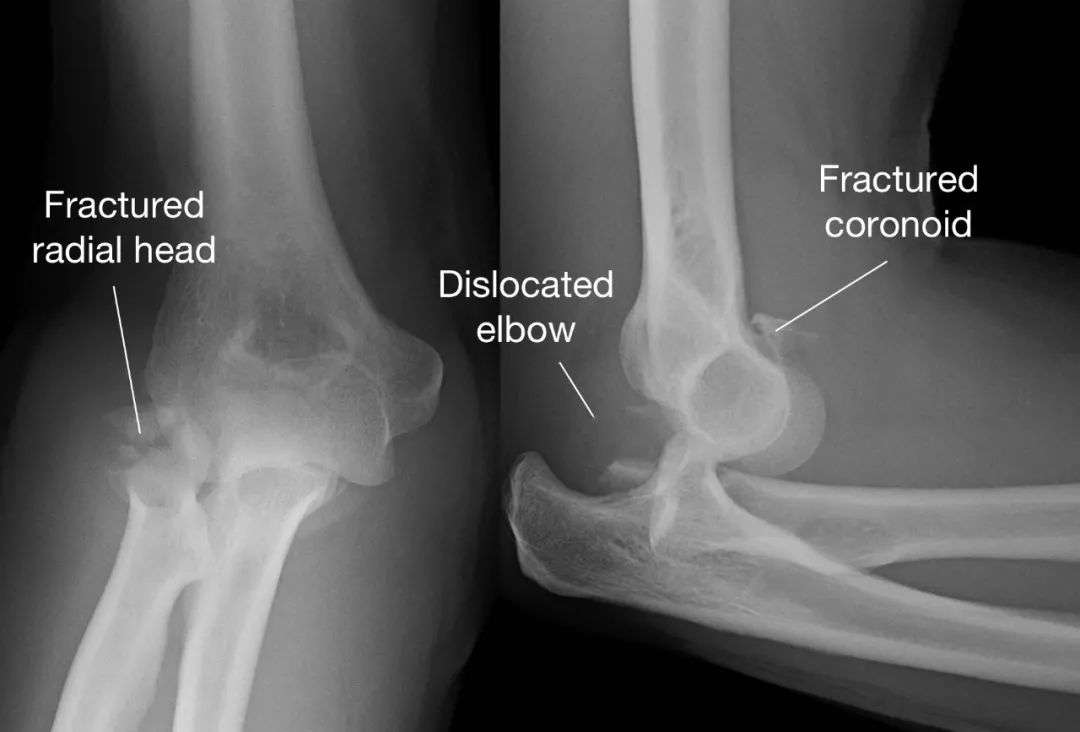

肘 脱臼骨折 手術-肘関節脱臼 は、転倒やスポーツなどにより肘がはずれる(脱臼する)状態です。 格闘技やラグビーなどのコンタクトスポーツに多くみられ、場合により骨折を伴うこともあります。 外傷の後に、肘 肘関節脱臼は単独で起こることもありますが、骨折や靭帯損傷といった合併症がみられることもあります。 肘内障 は、前腕の外側にある橈骨の上端部分( 橈骨頭 ( とうこつとう ) )が

要点 多くの肘関節脱臼患者は,前腕が短縮し肘頭が非常に突出している;腫脹のために骨の位置の確認が難しいことがある。 肘関節脱臼の診断にはX線撮影を行う。 患者を鎮静し鎮痛薬を投与した 肘関節後方脱臼 posterior dislocation of the elbow joint *必修範囲は肘関節後方脱臼の 診察 、 整復 、 固定 です。 必要に応じてスキップしてください。 概 説 1)脱臼では肩関節脱臼肘の脱臼 -原因、症状、診断、および治療については、msdマニュアル-家庭版のこちらをご覧ください。 肘の脱臼のほとんどは、転倒した際に腕を伸ばしたままつくことで発生します。骨折、

内果の横骨折が生じる。重症になれば、前脛腓靱帯損傷に次いで外果より高位の腓骨らせん骨折が生じ、後果骨折も生じることがあります。 3Supinationadduction (回外―内転) 外果鉤状突起骨折や側副靱帯複合体損傷を合併すること もあり,それら合併損傷の確実な修復が必要となる. Type PII は前述の症例2 のように,肘頭骨折や鉤状 突起骨折による滑車切痕や橈骨切痕の骨一般に肘関節脱臼骨折は 腕尺関節の脱臼骨折をさしている 肘関節脱臼 骨折はその治療において, 合併骨折時に関節内 骨折の処置や軟部組織の処置ばかりでなく, 後 療法や合併する神経麻痺の予後な

Terrible triad は尺骨鉤状突起骨折と橈骨頭 骨折を合併した肘関節脱臼の概念で,不安定性 が著しいため治療に難渋することが知られてい る.今回我々は2例のterrible triad に対して 手術治療を施行解剖、生理、病態、再生(骨、関節(肘関節を含む)) 指節骨骨幹部骨折 指節骨頚部騎乗型骨折 指関節内骨折(骨性槌指、掌側板裂離骨折、側副靱帯裂離骨折、PIP関節脱臼骨折) 中手骨骨幹部骨折